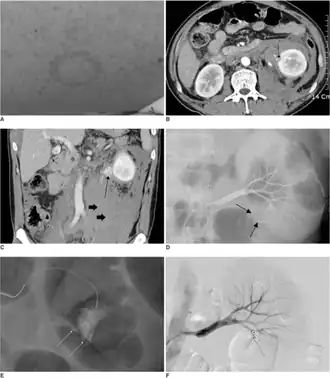

-

Mechanism of Hantavirus induced AKI[13] -